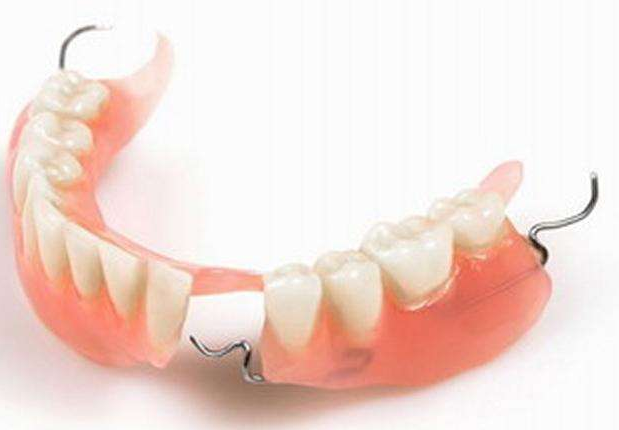

镶牙大体上分为两种,一种是活动假牙(也叫全口义齿),另一种是固定假牙(烤瓷牙)。它需要把患者缺失牙周边的两颗牙齿磨小,再一起套上牙冠,即一颗牙缺失,需要套上三个牙冠,相当于搭了一座桥。

而到了牙齿已经大部分脱落时,只能镶活动假牙。活动假牙需要依靠金属卡环和牙托固位,其咀嚼效能不高,会有不适感,部分人不容易适应,可能会因固位不稳引起假牙松动脱落。